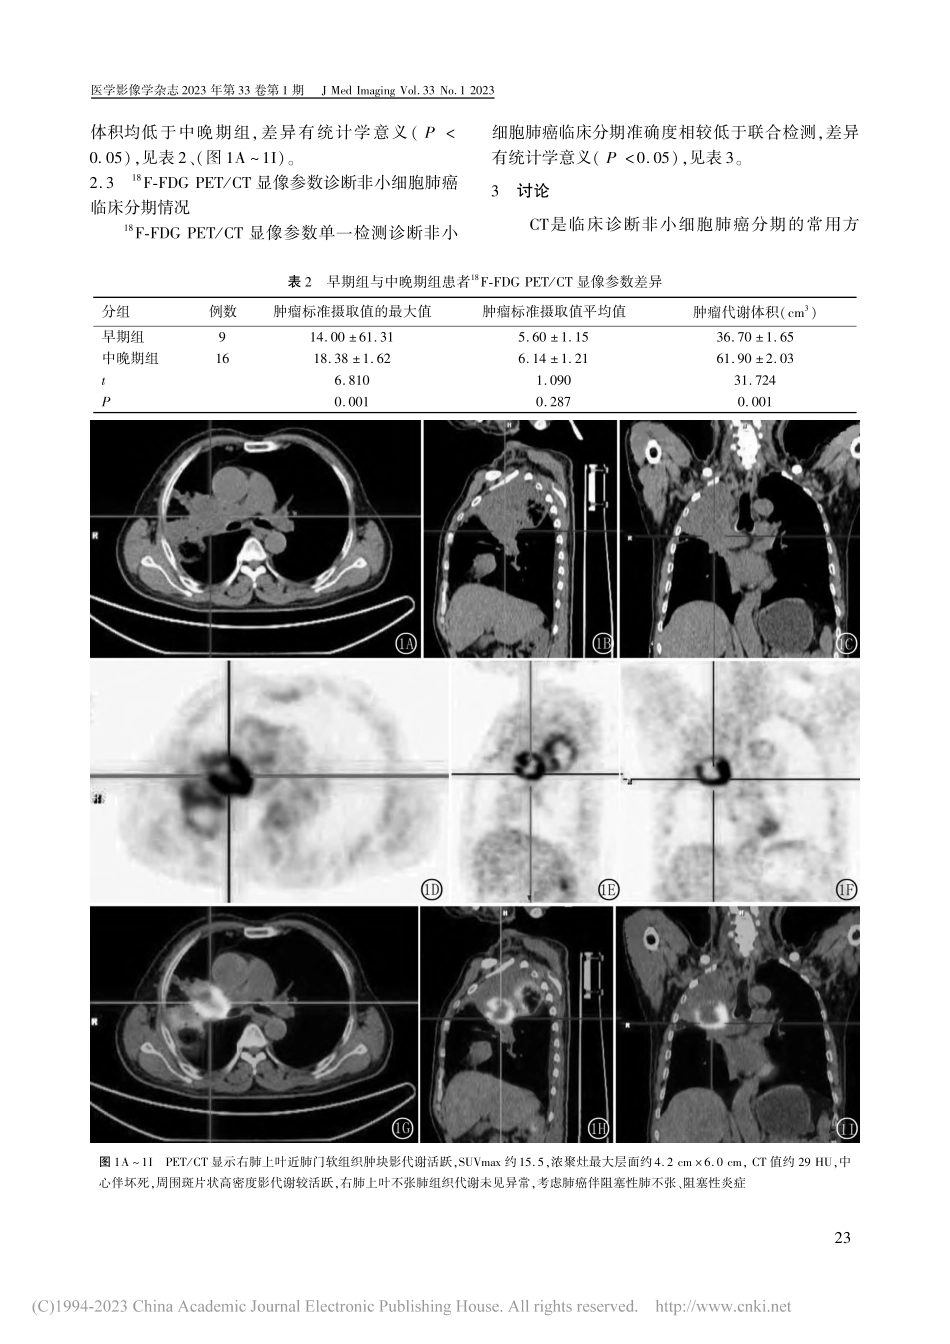

18F⁃FDGPET/CT显像在非小细胞肺癌分期中的价值徐华磊1,王大伟1,池泉1,马少华1,吴涛21.安徽省太和县人民医院核医学科安徽太和236600;2.安徽医科大学第一附属医院核医学科安徽合肥230022【摘要】目的探讨非小细胞肺癌开展18F⁃氟代脱氧葡萄糖(18F⁃FDG)正电子发射计算机断层显像/计算机断层扫描(PET/CT)的作用。方法选取非小细胞肺癌患者25例,均开展18F⁃FDGPET/CT显像检查,并采集病理组织标本开展病理检查,依据病理检查结果为患者实施临床分期,其中早期包含Ⅰ期和Ⅱ期患者,中晚期包含Ⅲ期和Ⅳ期患者。分析患者病理学检查情况;对比早期组与中晚期组患者临床资料、18F⁃FDGPET/CT显像参数;分析18F⁃FDGPET/CT显像参数诊断非小细胞肺癌临床分期情况。结果在25例非小细胞肺癌患者中,病理学检查提示Ⅰ期4例、Ⅱ期5例、Ⅲ期3例、Ⅳ期13例。9例属于早期组,16例属于中晚期组。中晚期组患者鳞状细胞癌抗原或癌胚抗原水平相较高于早期组,差异有统计学意义(P<0.05)。中晚期组肿瘤标准摄取值的最大值以及肿瘤代谢体积相较高于早期组,差异有统计学意义(P<0.05)。18F⁃FDGPET/CT显像参数联合检测诊断非小细胞肺癌临床分期准确度相较高于单一检测,差异有统计学意义(P<0.05)。结论非小细胞肺癌患者开展18F⁃FDGPET/CT显像检查,能够有效诊断疾病分期,发挥重要作用。【关键词】分期;非小细胞肺癌;体层摄影术,X线计算机;正电子发射计算机断层显像;18F⁃氟代脱氧葡萄糖中图分类号:R814.42;R734文献标识码:A文章编号:1006⁃9011(2023)01⁃0021⁃04Thevalueof18F⁃FDGPET/CTimaginginthestagingofnon⁃smallcelllungcancerXUHualei1,WANGDawei1,CHIQuan1,MAShaohua1,WUTao21.DepartmentofNuclearMedicine,TaiheCountyPeople'sHospital,Taihe236600,China2.DepartmentofNuclearMedicine,TheFirstAffiliatedHospitalofAnhuiMedicalUniversity,Hefei...